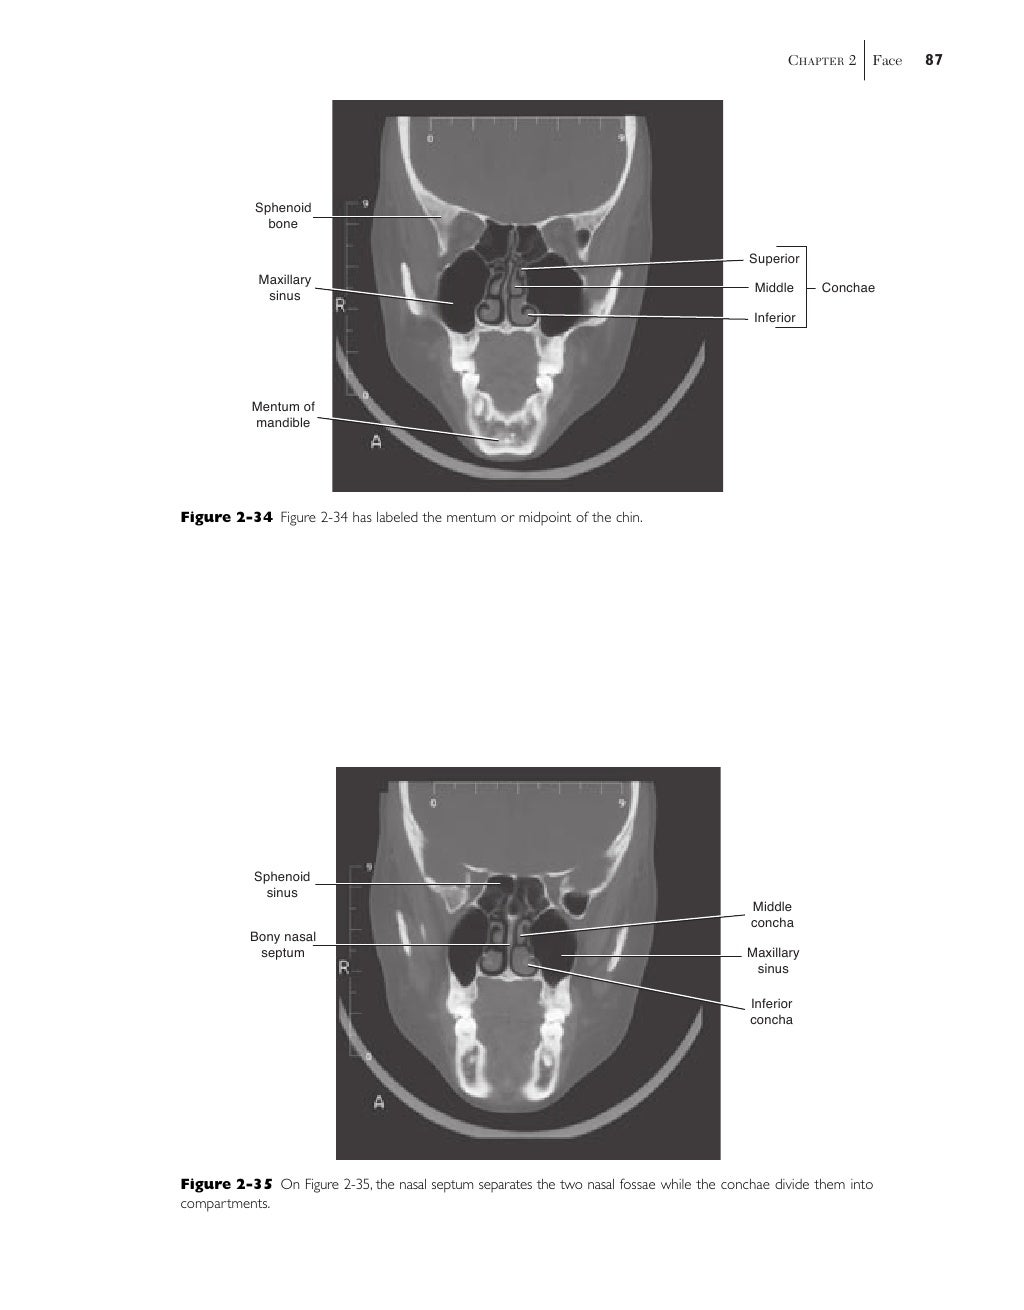

The Sectional Anatomy Study Tool is a web-based program to help the user learn human anatomy through images produced by CT-scan (computed tomography) and MRI (magnetic resonance imaging). The user can easily navigate through the stacks of image "slices" of each body section. The label "on" / "off" feature provides users an opportunity for self-assessment.… These changes warrant the need for medical professionals to under stand and identify human anatomy in both 2D and 3D images. Sectional anatomy emphasizes the physical relationship between internal structures.

For the benefit of medical students and those not accustomed to looking at sectional anatomy or images there are introductory 'helpful hints' offering a structured approach to identifying structures in this way. This atlas devotes 100 pages to the head and neck at 1-cm serial axial slices through the head and 1.5-cm slices through the neck.